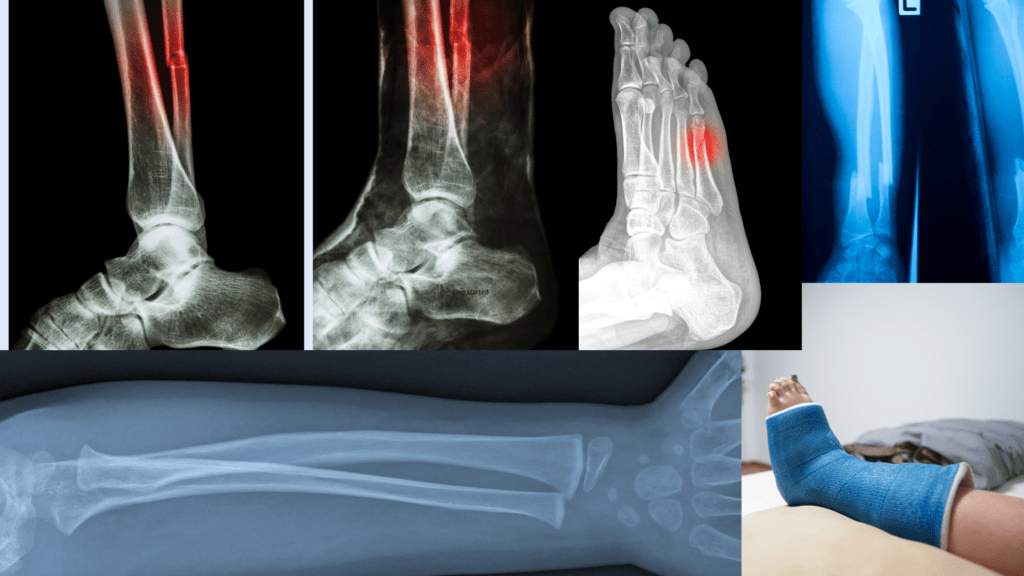

Can Weight Gain Cause Stress Fractures . Overweight individuals are at increased risk of suffering stress fractures in the lower back as well as the feet and lower extremities. It is a form of overuse injury from repetitive stresses on the bone. A stress fracture is a small, superficial crack in a bone. Spent three years studying the relationship between stress. An ohio state university (osu) study led by timothy l. Common types of stress fractures include:. Weak joints are more susceptible to oa. Causes of a stress fracture. Extra weight may put more stress on joints. Weight gain key to healing stress fractures. Bosscher says hormones, genetics and diet all can play a role in causing stress fractures, which may be one reason women. Having hypermobile joints or loose.

Understanding stress fractures